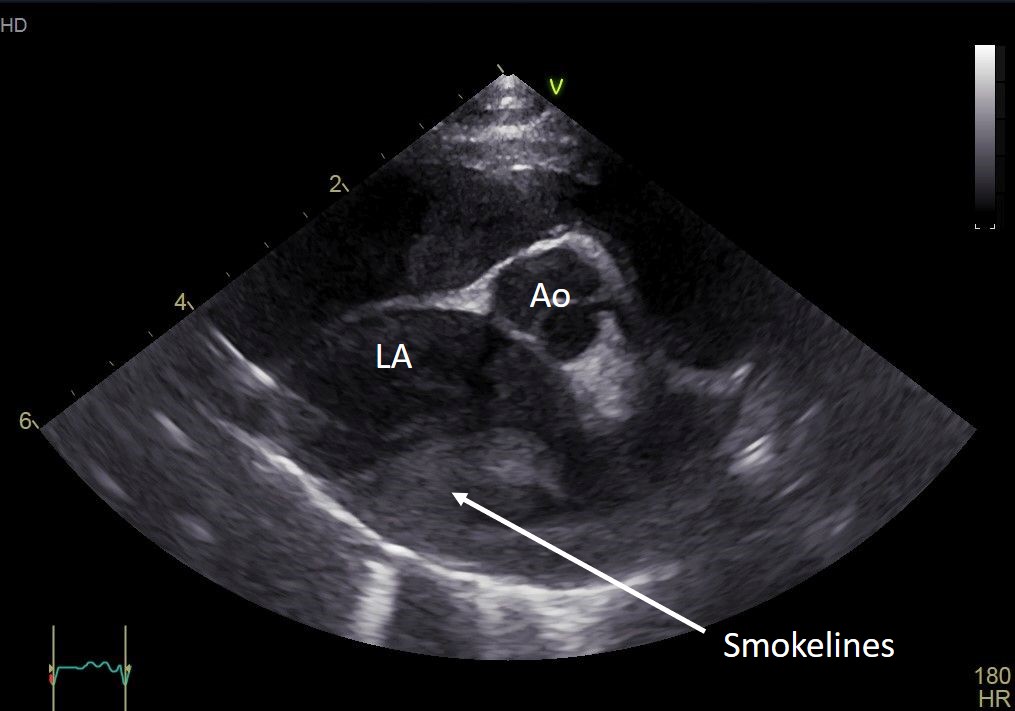

Das echokardiografische Bild einer HCM ist gekennzeichnet durch eine Zunahme der linksventrikulären Wandstärken über den Normbereich. Diese kann fokal oder generalisiert bestehen. Je nach Schweregrad der Erkrankung kann das linke Atrium vergrößert sein [Abb.1]. Bei deutlicher linksatrialer Stauung besteht grundsätzlich die Gefahr einer Thrombenbildung, die unter Umständen als sogenannter Spontankontrast im linken Atrium echokardiografisch darstellbar ist (sog. Smokelines, Abb.1).

Prädisponierte Rassekatzen sollten mittels Standard-of-Care-Echokardiografie auf das Vorhandensein einer Kardiomyopathie gescreent werden. Dies beinhaltet die Messung der linksventrikulären Dimensionen und Funktion sowie der linksatrialen Größe. Subjektiv sollte u. a. auf Papillarmuskelhypertrophie, endsystolische Kammerobliteration, Klappen- und Papillarmuskelabnormalitäten/ SAM, Spontankontrast/linkatrialen Thrombus u. a. geachtet werden.